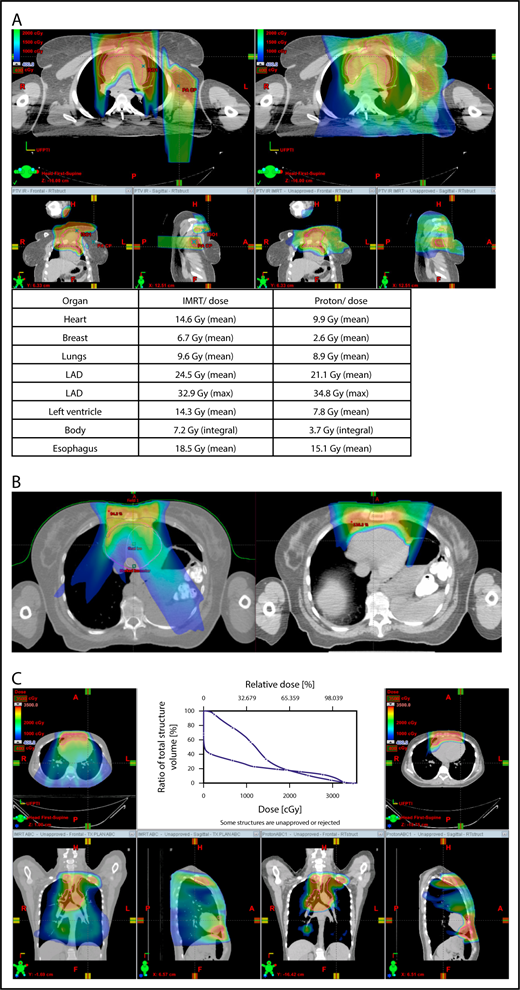

Axillary involvement at presentation. (A) Axial, coronal, and sagittal views of a proton plan (left) and an IMRT plan (right) for a patient presenting with axillary involvement. Use of proton therapy in this case spares the left breast. (B) Regardless of which treatment modality is chosen, IMRT (left panel) and proton (right panel), limiting the volume exposed to radiation should include attention to avoiding a low-dose bath. (C) Limiting lung dose. If avoiding the lung is the primary objective in a given patient, especially if the patient has received pulmonary toxic chemotherapy (eg, any combination of bleomycin, busulfan, gemcitabine, brentuximab, etc.), proton therapy may better spare the lungs by reducing the low-dose bath seen with photons.

Proton therapy can significantly reduce the radiation dose to the breasts by specifically using fields that enter posteriorly and stop short of exiting through the breast. Alternatively, if protons cannot be used, other methods of displacing the breast can be used instead, such as using an inclined board or physically moving the breast out the beam path. Figure 3A shows how using proton therapy can spare the breast in a case with axillary involvement.

When hilar disease needs to be covered, the dose to the breasts can increase, and avoiding the breasts becomes difficult with either modality (proton or photon). The choice of treatment modality for such cases must consider the doses received by other critical structures, such as the heart and lungs, especially in previously and heavily treated patients. However, in considering how to best limit the volumes exposed to radiation, avoiding “low-dose baths” is equally important (ie, irradiation of large volumes with low doses), regardless of which modality is used (Figure 3B).

Consideration of lung dose

With the advent of CT-based planning for mediastinal lymphoma, the dose to the lungs can now be correlated with the risk for pneumonitis. Restrictions on lung dose are encouraged to be V5 < 55%, mean lung dose < 13.5 Gy, and V30 < 20%. These values are more attainable with the use of DIBH.38 Although a mean lung dose of 13.5 Gy has been associated with a lower risk for pneumonitis, it is advisable to aim for a lower dose, which is quite often attainable when strict constraints are used. For example, when IMRT is used, it is important to limit the beams to some variation of anteroposterior beams, avoiding lateral beams. If avoiding the lung is the primary objective for a given patient, especially if that patient has received pulmonary-toxic chemotherapy (eg, bleomycin, busulfan, gemcitabine, brentuximab), proton therapy may better spare the lungs by reducing the low-dose bath seen with photons (Figure 3C).